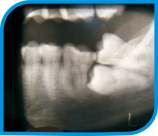

Cirurgia Bucomaxilofacial

É a especialidade da odontologia, que trata cirurgicamente as doenças da cavidade bucal e anexos, tais como: traumatismos e deformidades faciais, traumas. Em consultórios são exercidas cirurgias menores, sob anestesia local, onde são, por exemplo, removidos dentes inclusos, pequenos tumores benignos, cistos, lesões periapicais ou paradentais, implantes dentários, cirurgias para adaptações protéticas entre outras.